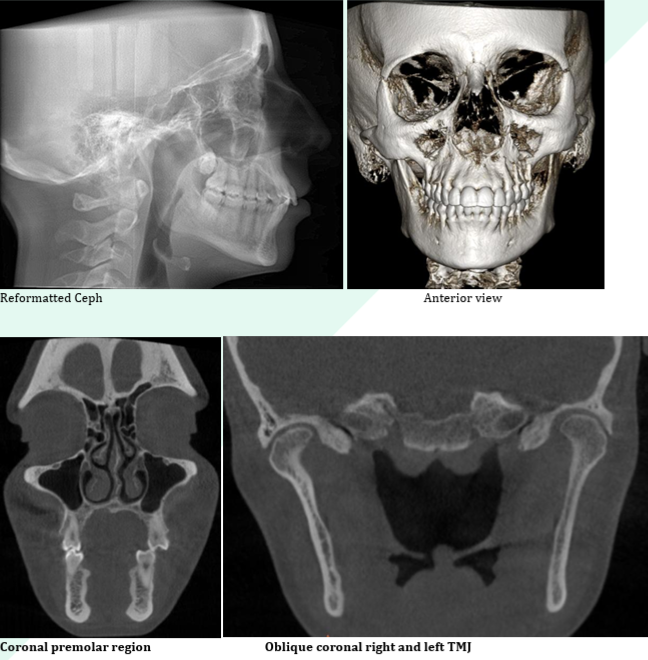

– Precise measurements and high-resolution annotated screenshots

Sinus evaluation

TMJ evaluation

Reporting of CBCT scans done your practice

Find some sample reports in PDF here: